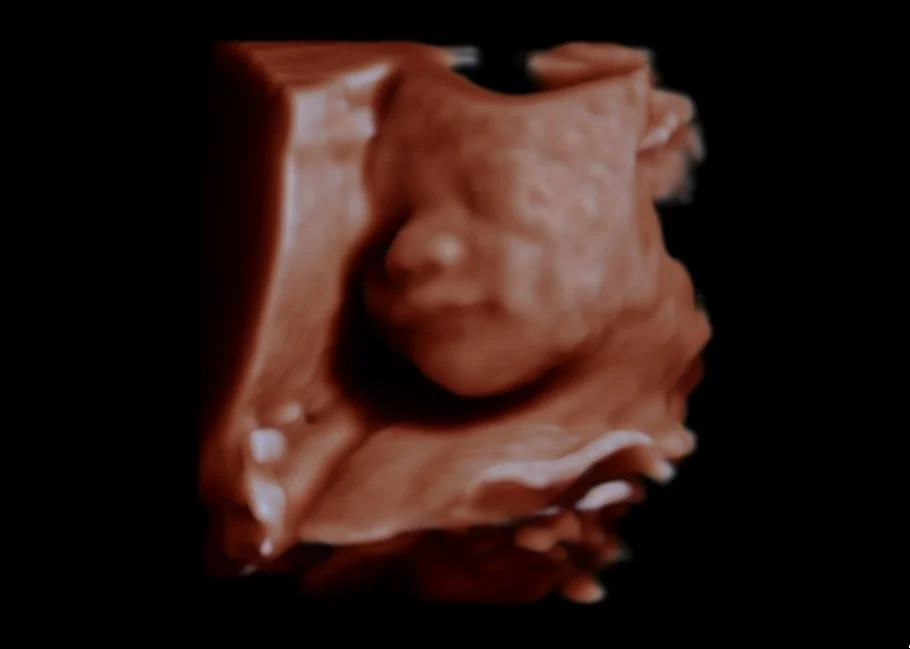

Obstetric and gynaecological ultrasound provides detailed imaging of the female pelvis and developing pregnancy. It is commonly used to monitor fetal growth and wellbeing, assess early pregnancy, and investigate gynaecological concerns such as pelvic pain or abnormal bleeding.

Obstetrics & Gynaecology

Dating Scan

Early Structural (12-16 Weeks) Scan*

Morphology*

Nuchal Translucency Scan*

Third Trimester